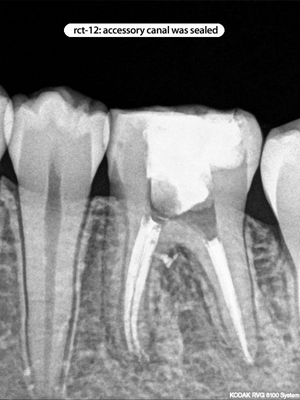

Root Canal Cases